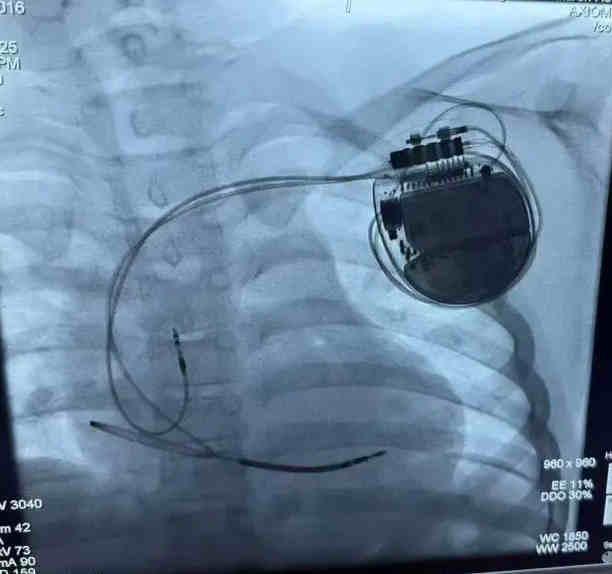

經(jīng)過(guò)充分的術(shù)前準(zhǔn)備,李磊團(tuán)隊(duì)為小宇實(shí)施了ICD植入術(shù)。手術(shù)在局部麻醉下進(jìn)行,團(tuán)隊(duì)?wèi){借精湛的技術(shù),精準(zhǔn)地將電極導(dǎo)線(xiàn)經(jīng)靜脈植入小宇的右心室,并將ICD脈沖發(fā)生器埋藏于左胸前皮下。整個(gè)手術(shù)過(guò)程順利,耗時(shí)約1.5小時(shí),小宇無(wú)明顯不適。術(shù)后,小宇在醫(yī)護(hù)人員的精心照料下恢復(fù)迅速,精神狀態(tài)良好,食欲也逐漸恢復(fù)。經(jīng)過(guò)一周的觀察與護(hù)理,小宇順利出院,回到了溫暖的家庭懷抱。從此,他再也不用擔(dān)心暈厥的困擾,可以像其他孩子一樣盡情玩耍、快樂(lè)成長(zhǎng)。